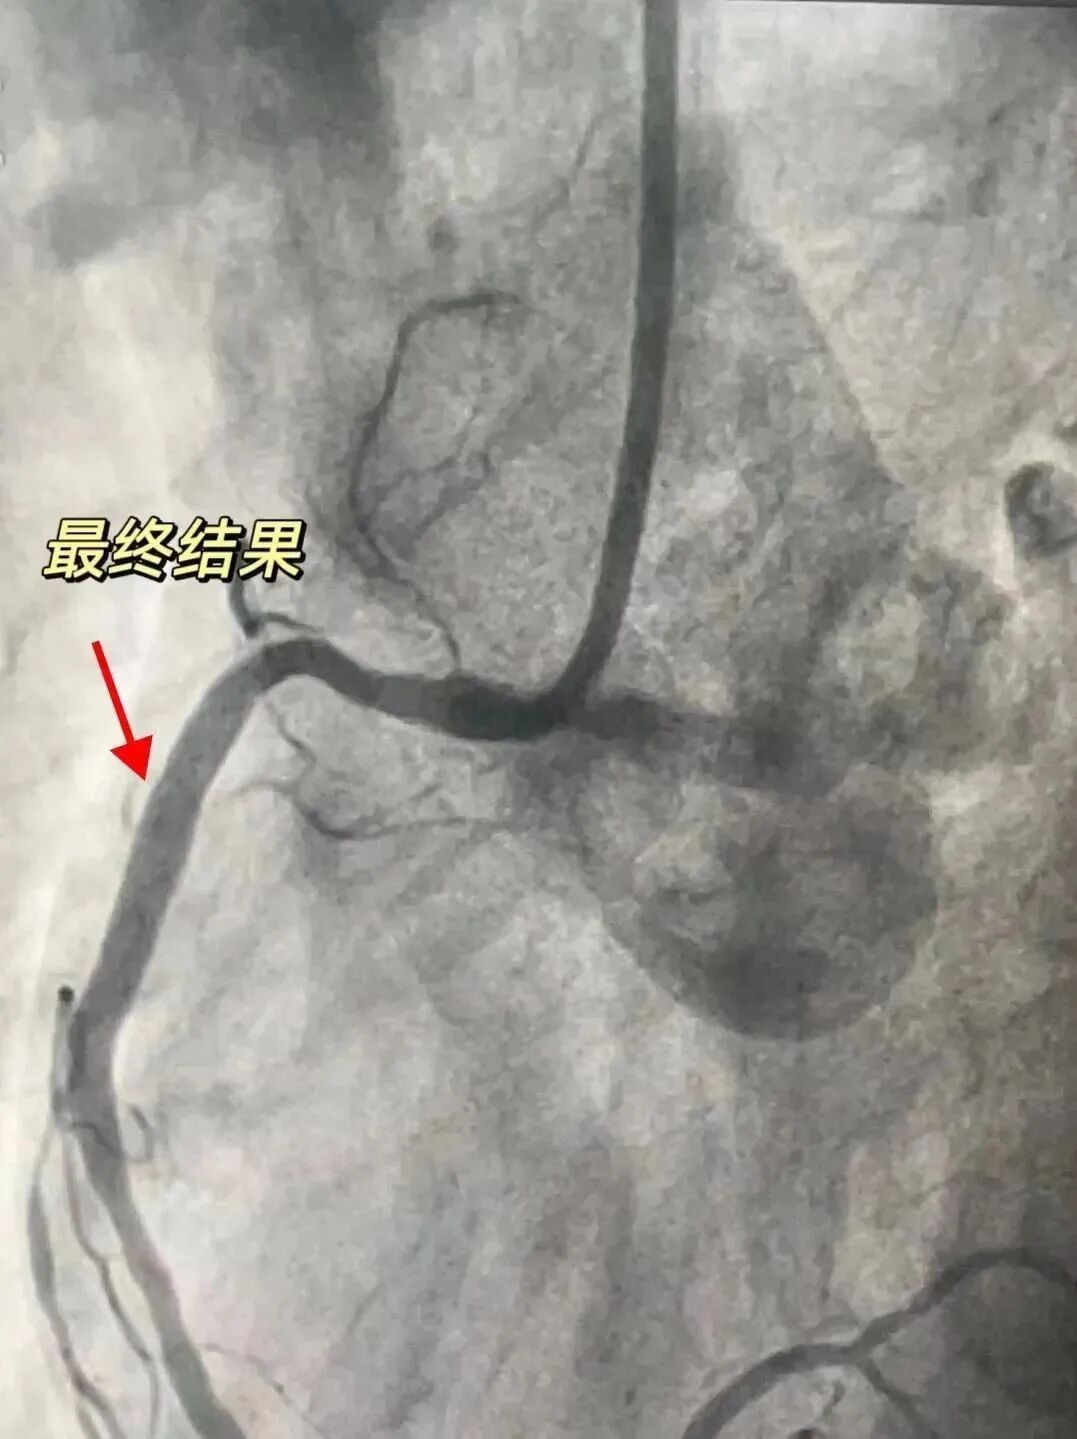

“震波球囊就位,释放脉冲!”术中,心内科团队将3.0*12mm Shockwave球囊导管顺利送至钙化病变处,在钙化最严重处进行4组血管内冲击波治疗。治疗后复查IVUS,提示钙化被震裂打开,裂痕明显,钙化狭窄处直径明显增大,这代表原来“石头”似的钙化斑块有些被“震”断了,心内科团队成功运用这种新方法打开患者血管的“紧箍咒”。

“难点”被击破后,团队顺利为患者植入支架一枚,复查造影及IVUS提示新植入的支架扩张充分,贴壁良好。术后,患者即刻表示胸闷、胸痛症状均得到缓解。